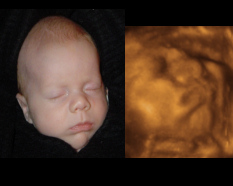

Diagnostic imaging over the last 50 years: research and development in medical The University of Chicago, 5841 South Maryland Avenue, Chicago, IL 60637, USA E-mail: k-doi@uchicago.edu Received 5 March 2006 Figure 23. 3D ultrasound image obtained by fusion of a B-mode image for ... Doc Viewer